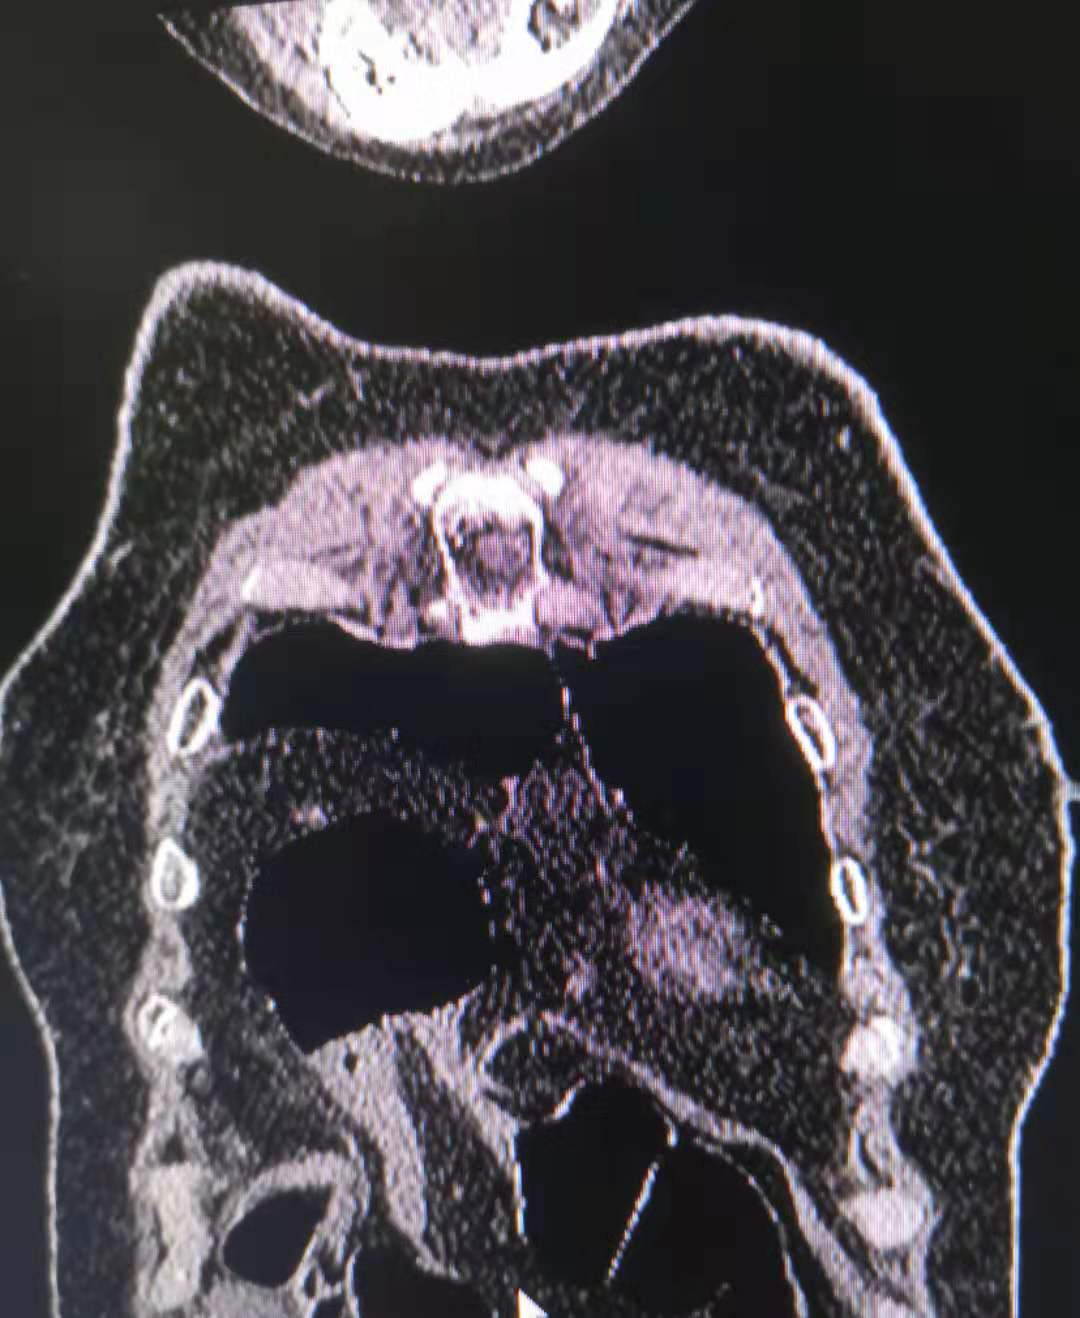

今天医院收到一位腰椎骨折的患者,还伴随有长期腰痛胸痛和消化不良,外院诊断为腰椎单纯骨折并胸部巨大脂肪瘤。在我院高档CT、磁共振的检查下,却是另外一种发现。

我们的设备,清楚地显示出外院照片没有发现的细节。

单纯腰椎骨折的背后,还发现了一个被压碎的血管瘤。而且其余椎体还有几个小的血管瘤。这就不是单纯骨折,而是病理性骨折。符合患者在轻微运动下就发生骨折的事实。

针对胸部的脂肪瘤,我院设备强大 的再重建功能显示,患者的膈肌上的巨大肿块影中有奇怪的积气现象。

往下追查,看到肿块来源于腹部,其中奇怪的气体影,是腹部的肠管。

最后的结论是腹部肠管及肠系膜疝入胸腔,患者长期的消化不良的现象得到了解释。